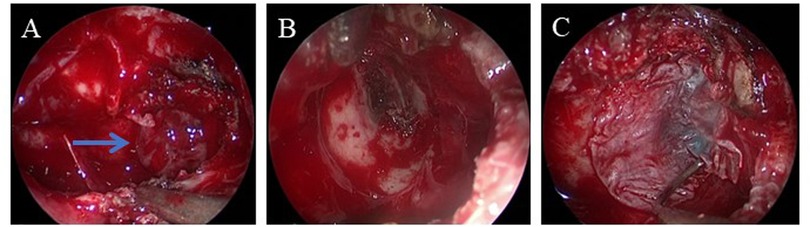

Figure 3

Medical endoscopic images labeled A, B, and C show a sequence of procedures or conditions. Image A features a blue arrow pointing to a specific area. The images display various tissues in red hues, indicating examination or surgery.

Figure 3. Intraoperative images. (A) Herniated meningeal and brain tissues in the left sphenoid sinus. (B) After removing the herniated tissues, a bone defect in the left lateral recess of the sphenoid sinus is found, together with clear liquid outflow. (C) Muscle and fascia lata from the lateral thigh are used to repair the defect. The arrow indicates the herniated meningeal and brain tissues.

An endoscopic nasal repair was performed using a transmaxillary posterior wall approach after obtaining preoperative informed consent and ascertaining the patient's fitness for anesthesia. During the surgery, the anterior wall of the sphenoid sinus was removed and the maxillary sinus ostium was widened. Posterior dissection was carried out along the maxillary sinus toward the root of the pterygoid process. The bony structures of the pterygoid process root and the posterior wall of the maxillary sinus were then removed. A bone defect was observed in the left lateral recess of the sphenoid sinus, with herniation of meningeal and brain tissues, and visible CSF leakage (Figure 3). After removing the herniated brain tissue and CSF, a multilayered repair was performed using the inside-out technique, i.e., using muscle and fascia lata from the lateral thigh, gelatin sponge, and iodoform gauze to close the defect. Postoperatively, the patient was treated daily with 20% mannitol to reduce intracranial pressure and ceftriaxone to prevent infection for 12 days. The iodoform gauze in his left nasal cavity was removed 10 days after the surgery. The patient was then discharged without a nasal drip, fever, headache, or any other complications. The postoperative follow-ups at 1 and 6 months confirmed the absence of CSF rhinorrhea and demonstrated successful reconstruction of the traumatic defect (Figure 1B).